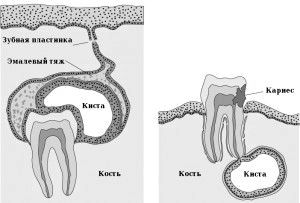

Кіста верхньої щелепи, як і кіста нижньої щелепи, не має особливих характерних ознак і симптомів. Виявляється зазвичай випадково при рентгенологічних дослідженнях. Кісти щелеп можуть бути вродженими, однак найчастіше щелепні кісти - результат періодонтиту. Періодонтит - запалення тканин періодонта, що виникає або в результаті неправильного, неякісного лікування, або несвоєчасного звернення до стоматолога. Періодонтит може бути гострий і хронічний. Саме хронічні форми призводять до утворення кіст. Це захворювання в своїй течії проходить 3 стадії розвитку: фіброзну, гранулюючу, гранулематозний.

Гранулююча форма характеризується розростанням нових кровоносних судин в області верхівки кореня. На рентгені при цьому виявляються нечіткі межі деструкції кісткової тканини у вигляді «вогнищ полум'я». При прогресуванні процесу захворювання переходить в стадію Гранулематозний. У цей час відбувається розпад тканин і формування демаркаційної лінії, що відмежовує здорові тканини від руйнуються. Тобто, таким чином відбувається формування гранульоми. Вона має чіткі межі, часто овальної форми. Розміри її до 0,5 см. При розростанні вогнища до 0,8 см говорять про виникнення кістогранулеми. Все, що більше в діаметрі 0,8 см - кіста.

Кіста нижньої щелепи найчастіше локалізується в області багатокореневих зубів, а саме в області перших молярів. Кіста зубів і коренів на верхній щелепі найчастіше локалізується на премолярах і молярах.